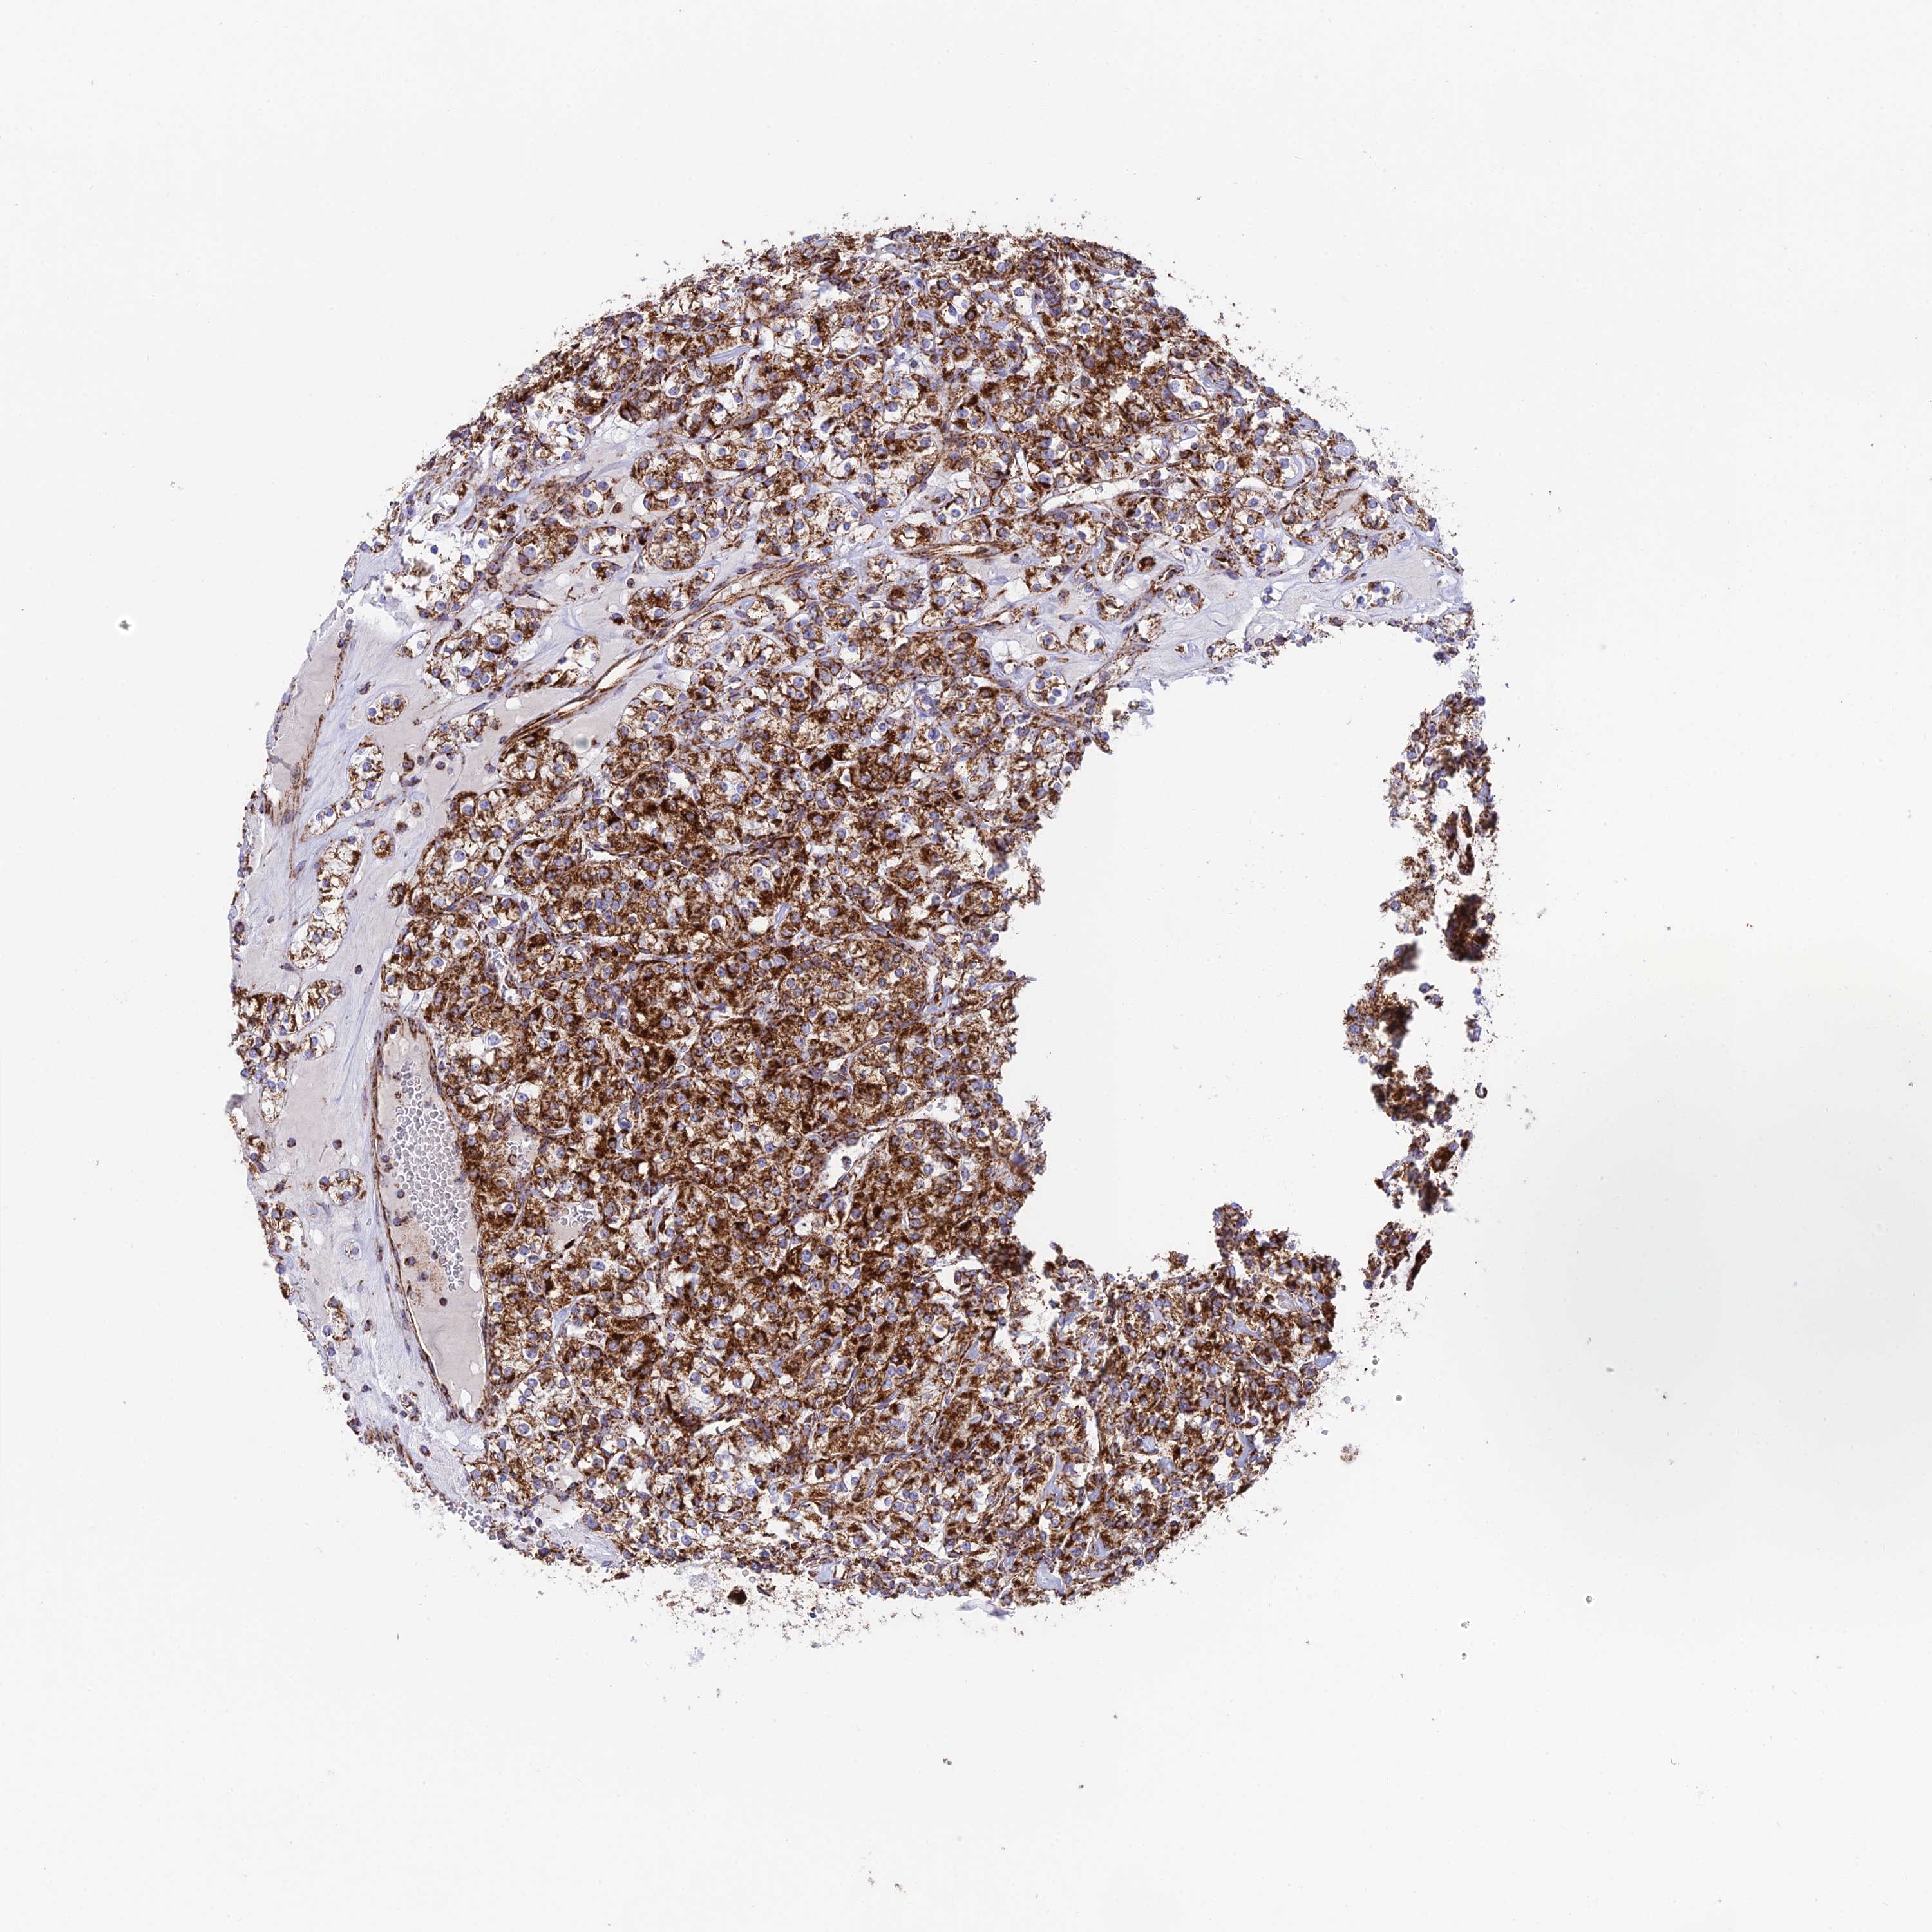

KIDNEY RENAL CLEAR CELL CARCINOMA (VALIDATION) - Interactive survival scatter ploti

The Survival Scatter plot shows the clinical status (i.e. dead or alive) for all individuals in the patient cohort, based on the same data that underlies the corresponding Kaplan-Meier plots. Patients that are alive at last time for follow-up are shown in blue and patients who have died during the study are shown in red.

The x-axis shows the expression levels (FPKM) of the investigated gene in the tumor tissue at the time of diagnosis. The y-axis shows the follow-up time after diagnosis (years). Both axes are complimented with kernel density curves demonstrating the data density over the axes. The top density plot shows the expression levels (FPKM) distribution among dead (red) and alive patients (blue). The right density plot shows the data density of the survived years of dead patients with high and low expression levels respectively, stratified using the cutoff indicated by the vertical dashed line through the Survival Scatter plot. This cutoff is automatically defined based on the FPKM cutoff that minimizes the p-score. The cutoff can be changed by dragging the vertical line or by entering a cutoff value in the square labeled "Current cut-off".

Under the Survival Scatter plot the p-score landscape (black curve; left axis) is shown together with dead median separation (red curve; right axis). Dead median separation is the difference in median mRNA expression between patients who have died with high and low expression, respectively. It is calculated as follows: median FPKM expression of dead patients with high expression - median FPKM expression of dead patients with low expression. This is intended to aid the user in visually exploring custom cutoffs and the associated p-scores and dead median separation.

Individual patient data is displayed and can be filtered by clicking on one or more of the category buttons on the top of the page. Categories describing expression level and patient information include: high, low, alive, dead, female, male and tumor stages. The scale of the x-axis can be toggled between linear and log-scale by clicking on the "x log" button. Mouse-over function shows TCGA ID, patient information and mRNA expression (FPKM) for each patient.

& Survival analysisi

Kaplan-Meier plots summarize results from analysis of correlation between mRNA expression level and patient survival. Patients were divided based on level of expression into one of the two groups "low" (under cut off) or "high" (over cut off). X-axis shows time for survival (years) and y-axis shows the probability of survival, where 1.0 corresponds to 100 percent.

CHCHD3 is not prognostic in Kidney Renal Clear Cell Carcinoma (validation)

Best expression cut offi

Based on the FPKM value of each gene, patients were classified into two groups and association between prognosis (survival) and gene expression (FPKM) was examined. The best expression cut-off refers the FPKM value that yields maximal difference with regard to survival between the two groups at the lowest log-rank P-value. Best expression cut-off was selected based on survival analysis .

When clicking on this number, the vertical dashed line indicating cut-off, the interactive survival plot, and the Kaplan-Meier curve will be adjusted to show results based on the best expression cut-off.

: 60.84

P scorei

Log-rank P value for Kaplan-Meier plot showing results from analysis of correlation between mRNA expression level and patient survival.

N/A

TCGA RNA samplesi

RNA-seq data is reported as average FPKM (number Fragments Per Kilobase of exon per Million reads), generated by the The Cancer Genome Atlas (TCGA) .

Normal distribution across the dataset is visualized with box plots, shown as median and 25th and 75th percentiles. Points are displayed as outliers if they are above or below 1.5 times the interquartile range. FPKM values of the individual samples are presented next to the box plot.

Average pTPM 57.9

Number of samples 100